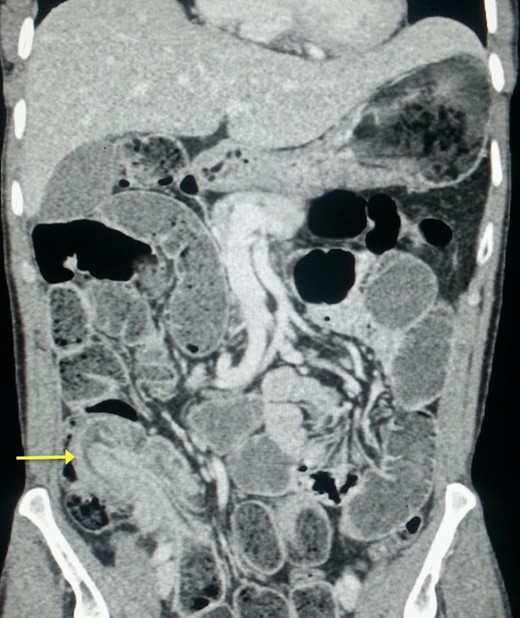

A plain abdominal radiography suggested a bowel obstruction, by showing multiple air-fluid levels. Biological results were the following: hemoglobin: 13,5 g dl−1, hematocrit rate: 42,5%, white blood cell count: 8×103 mm−3, creatinine = 18 mg L−1, serum Na: 139 m Eq L−1, serum K: 3.4 m Eq L−1. The contrast-enhanced CT showed a target mass localized in the right iliac fossa, and was suggestive of ileocecal intussusception without specifying the underlying cause (Fig. 1). While coronal reconstruction showed a « sausage-shaped mass » (Fig. 2). Moreover, there was some lymphadenopathies surrounding the target mass, and a small amount of abdominal effusion.

The classic ‘target mass’ picture on CT scan as found in our case, is pathognomonic of intussusception [6]. It consists in a central dense area and a halo of low attenuation being respectively the intussusceptum and the edematous intussuscepiens [7, 8]. In a sagittal view, we found the classical « sausage sign » in our patient. Moreover, CT scan may identify the underlying cause of the intussusception [1]. The common sites of occurrence of this condition are the junction between the movable segments of the intestine and segments that are relatively fixed as in our case.